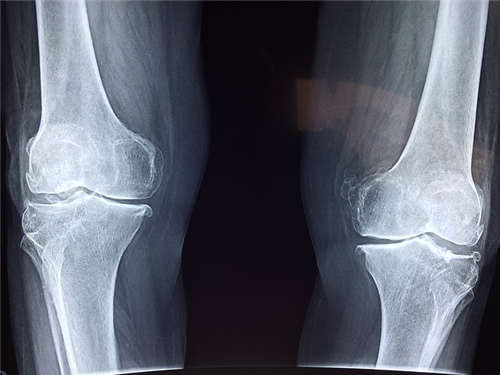

關節炎。症狀以急性關節炎多見,典型的關節炎出現在尿道或腸道感染後1~6周。呈急性發病。多爲單一或少關節炎,非對稱性分布,呈現伴關節周圍炎的臘腸樣指(趾)。關節炎一般持續1~3個月,個别病例可長達半年以上。主要累及膝及踝等下肢大關節。肩、腕、肘、髋關節及手和足的小關節也可累及。受累關節呈熱、腫脹、劇痛和觸痛。膝關節常有明顯腫脹及大量積液。背部不适常放射到臀部和大腿。在卧床休息和不活動時加重。肌腱端病的典型表現是跟腱附着點炎。初次發病症狀通常在3~4個月内消退,并可恢複正常。但有複發傾向,某些患耆可在反複發作過程中發生關節畸型、強直、骶髂關節炎和(或)脊柱炎。